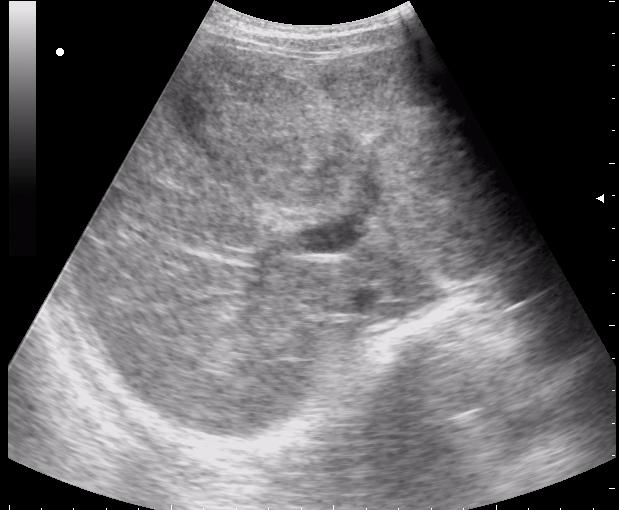

наезд большой черной Прады на маленькую (13кг) 5-летнюю девочку.

получает Медаксон, рабочая версия - изменение желчного пузыря вследствии травмы (шепотом - рекомендация хирургу сменить антибиотик)

сегодня был селезёночный день.